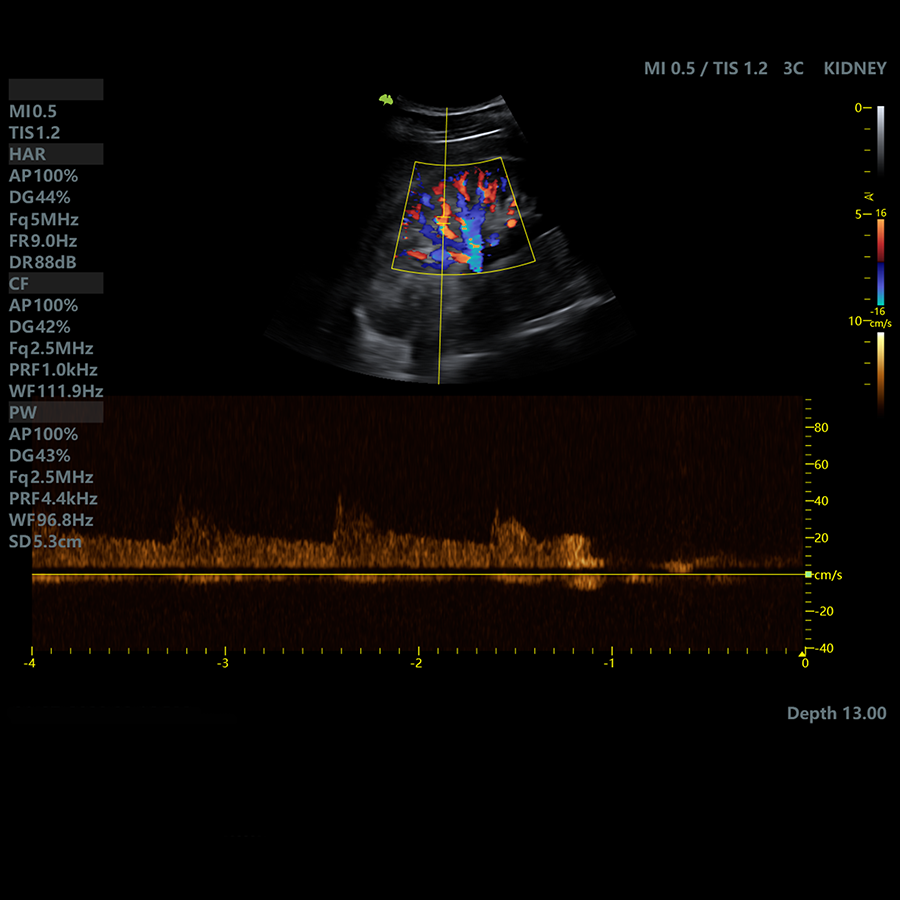

Doppler

- Modo CFM (Color)

- Modo PW (Pulsado)

- Trazo automático de espectro